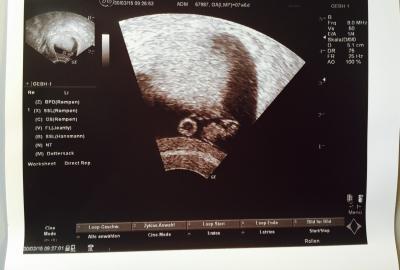

Hallo, erster Schock von letzter Woche ist verdaut und nun schon die nächsten Ängste...Am Montag war ich vorsichtshalber mal beim FA, nachdem letzte Woche einfach alle SS-Symptome wegwaren und ich Angst bekam. Mein FA hat nachgesehen, Herzchen schlägt und er meinte es ist alles ok. Aber ich mache mir unheimlich Sorgen wegen der Form der Fruchthöhle, sie sieht aus wie ein Bumerang, hat so eine V-Form. Seht selber am Bild. Hab gelesen sie sollte rund sein... Der Embryo war gestern bei 7+6 nur 1,1 cm groß. Das ist doch zu klein oder? Letzte Woche bei 6+6 war er 0,8 cm. Das kleine Würmchen ist nicht viel gewachsen. Mein FA hat aber nix schlechtes dazu gesagt. Einfach nur das wir uns ja in 3 Wochen sehen.... War das bei jemandem auch so? Wäre sehr froh über eure Antworten. Lg

Bild zu Angst! 7+6 - Sehr unförmige Fruchthöhle & zu kleiner Embryo? - Schwanger - wer noch? Rund um die Schwangerschaft

vielleciht kann ich mich auch irren, aber für mich sieht das so aus, als wäre das so abgebildet nicht die Fruchthöhle, sondern als wäre die nur angeschnitten und nicht richtig komplett drauf. hast du ihn zur Form der Fruchthöhle befragt?? bei mir im US war auch so ein streifen einmal quer durch, aber das waren Artefakte vom US-Gerät und nicht wirklich da..

Danke für deine Antwort. Nein, hab ihn leider nicht gefragt wegen der Form. Hab mich dann Zuhause erst hingesetzt mit dem Bild und hab zum grübeln angefangen. Denke schon das sie komplett drauf ist, oben links sieht mans ja kleiner, ich denke da ist sie ganz drauf. Ich will und werde jetzt einfach positiv denken Hoffe einfach das alles gut wird.